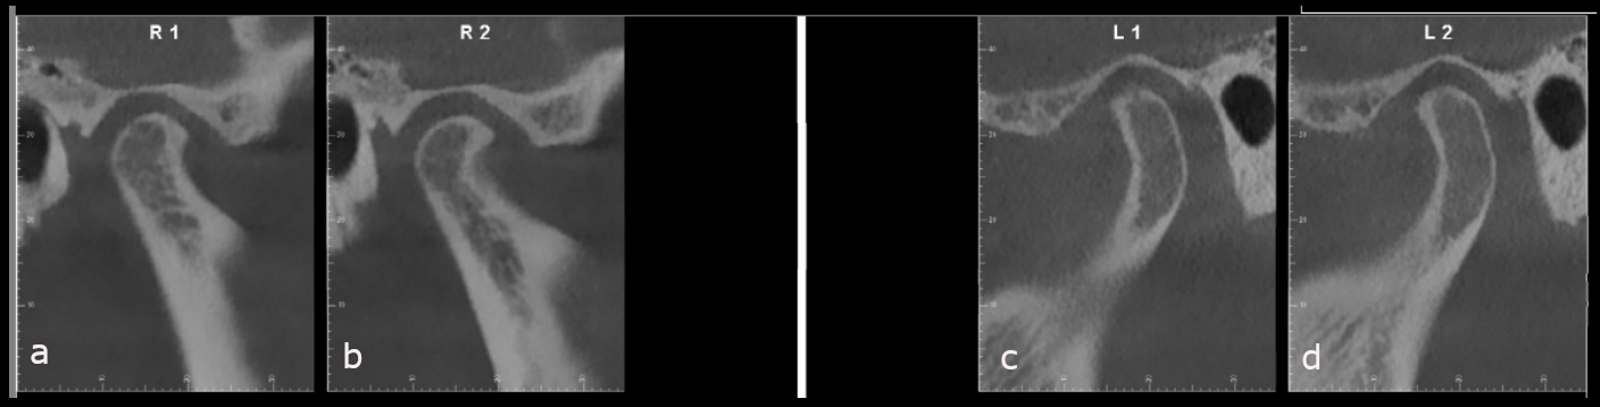

Initial treatment in 29 stages was planned, by which point the final occlusal results would have been obtained. We began with the placement of attachments and micro-screws in the maxillary arch for posterior intrusion (Fig. 18). After seven months of treatment and in the 20th stage, we introduced the FAS STOP and GO concept and took new records to prepare for the second phase of aligner treatment (Fig. 19). Thanks to STOP and GO, it is possible to achieve better tracking so that aligners fit properly and shorter treatment times using fewer aligners. This is the advantage of planning in different stages. It helps us achieve all our treatment goals on a consistent basis, and treatment efficiency is much higher.

The second phase of treatment began with the placement of new attachments (Figs. 20–22) and consisted of 12 stages, during which we continued to intrude the maxillary molars, centre the mandibular midline and level the occlusal planes. This phase lasted for four months. The total treatment involved 32 stages over 11 months, and all the treatment goals were achieved (Figs. 23–25).

The final dental panoramic tomogram showed the correct levelling of the occlusal planes and root positions (Fig. 26). The final cephalometric tracing showed closure of the facial angle thanks to the posterior intrusion and mandibular auto-rotation (Figs. 27 & 28). Mandibular antero-rotation shortens the lower facial third, improving lip competence and ultimately the facial profile. The CBCT images of the TMJs showed the correct position of the condyles within the glenoid fossae (Fig. 29). When looking at the airway on the CBCT scan, we also saw an improvement of the patient’s airway (Fig. 30).